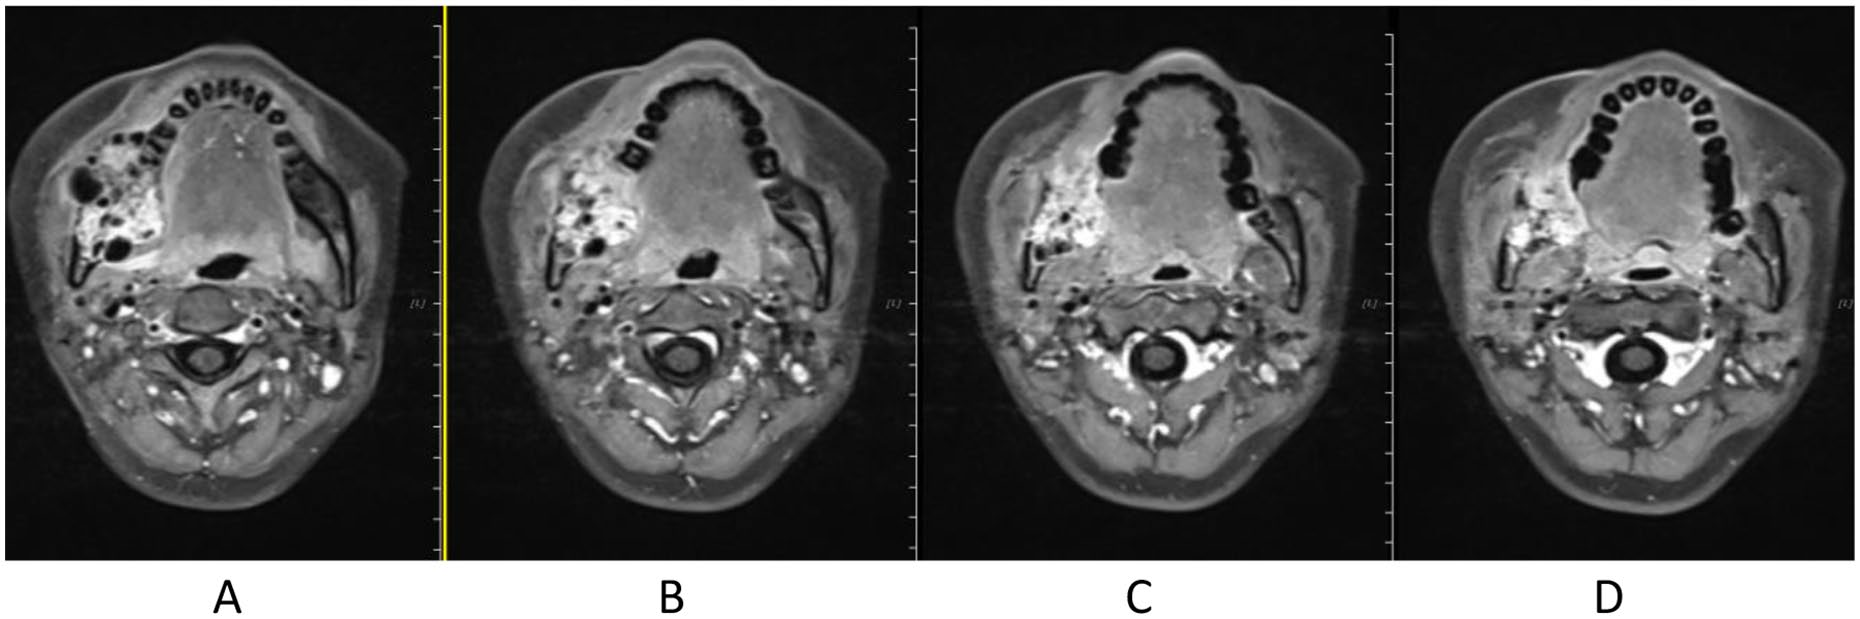

Treatment was tolerated well. During and after CIRT, there was only grade 2 skin (Figure 2) and oral mucosa acute adverse event, and no grade ⩾3 RTOG acute effect. During and after CIRT, her pain in the right mandible is continued but never aggravated, but painkiller is not needed; 6-month post completion of radiotherapy, she was in a very good clinical state, and the pain in the right mandible resolved completely. One to three months after CIRT, there were no significant changes of tumor size on MRI (Figures 3–6), just intensity of contract enhancement gradually diminished on contract-enhanced T1-weighted MRI; from 6months on, the size of the tumor decreased gradually (Figure 7); up to 16months after CIRT, it regressed to 3.6cm×3.2cm×1.7cm; and on 19months after CIRT, it regressed to 3.6cm×3.2cm×1.7cm, and the efficacy evaluation is PR (partial response) (Figures 8–10).

Figure 7. 6 months after CIRT.

Figure 8. 12 months after CIRT.